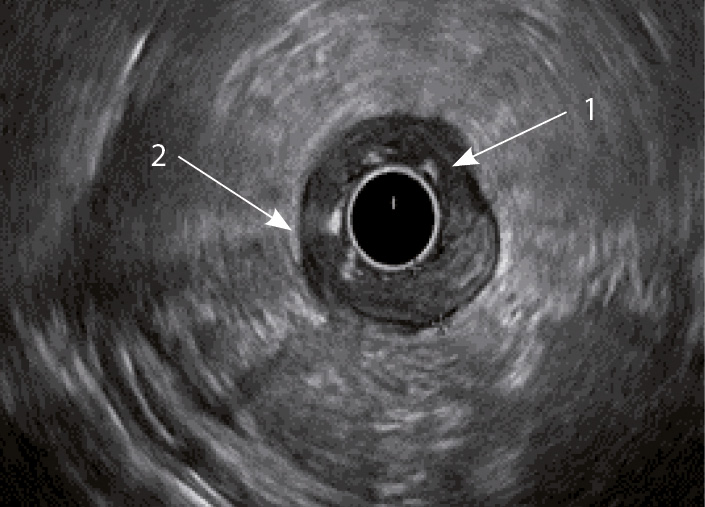

Рис. 2. Эндосонографическая картина стенки толстой кишки в норме

Рис. 3. Эндосонографическая картина толстой кишки при язвенном колите; 1 – утолщение слизисто-подслизистого слоя; 2 – утолщение стенки толстой кишки

Кишечная стенка статистически значимо чаще утолщалась за счет слизисто-подслизистого слоя при ЯК, чем при БК: в 82 и 7,14% соответственно; диагностическая чувствительность данного признака была 82%, а специфичность – 93% (табл. 1). При БК изменение стенки толстой кишки за счет трансмурального утолщения выявлялось статистически значимо чаще (68%), чем при ЯК (9%) (чувствительность 68%, специфичность 91%). Статистически значимых различий в частоте изменений мышечного слоя кишки отмечено не было. Только при БК в 68% случаев отсутствовала дифференцировка слоев кишечной стенки в фазе обострения (чувствительность и специфичность признака составили 68 и 100% соответственно) (см. рис. 4). При ЯК на фоне «смазанности» слизисто-подслизистого слоя у всех больных можно было визуализировать мышечный и серозный слои (см. табл. 1, рис. 3).